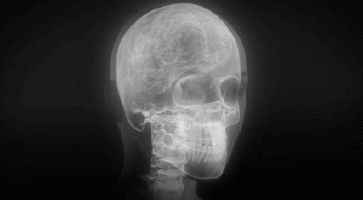

Este 3 de julio se celebra en España el segundo Día de la Tecnología Sanitaria al conmemorarse el fallecimiento – hace 81 años – de Maria Salomea Skłodowska-Curie, conocida habitualmente como Marie Curie, pionera en el campo de la Radiactividad, por lo que recibió el Nobel de Física en 1903, junto con Henri Becquerel y Pierre Curie.